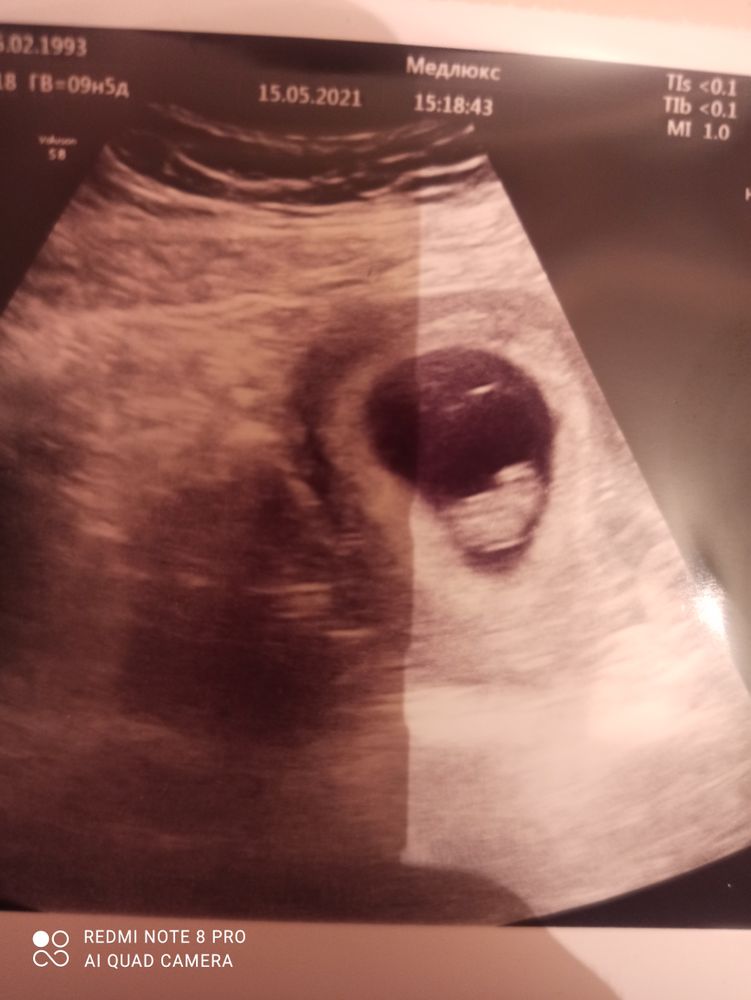

Результаты УЗИ

Здравствуйте! Сегодня сходила на УЗИ. По м срок 9 недель и 5 дней, по кто на неделю меньше. Как и предполагалось что овуляция поздняя, значит в сроках расхождение будет. Самое главное с малышом все в порядке, сердечко бьётся, растём 😍 По УЗИ уже можно определить где головка, где ножки. Уже маленький такой человечек. Оставлю фото УЗИ на память здесь. Ещё один момент, врач сказала что с уверенностью могу вам сообщить 80 процентов даю, что у вас девочка будет. Вот как на таком сроке можно это определить, там же не видно ничего? Она уверяла, что поверьте моему опыту, я ещё не ошибалась. Кружок пока не закрашиваю, буду ждать первого скрининга. Но в душе уже настроилась на дочурку 🤰😍😍😍